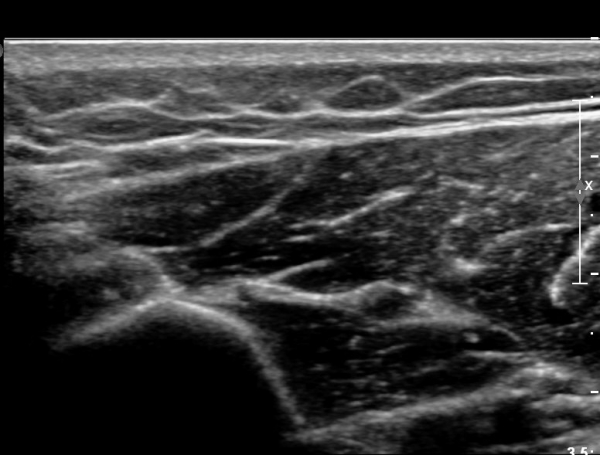

¿ä°ñ °í¶û ¸»´Ü¿¡¼­ ¿ä°ñ½Å°æ Á¾´Ü¸é°Ë»ç»ó ¿ä°ñ½Å°æÀÇ Àú¿¡ÄÚ ºÎÁ¾°ú Áß°£ ºÎÀ§¿¡

±¹¼ÒÀû ÇùÂøÀÌ °üÂûµÈ´Ù(»çÁø 5).